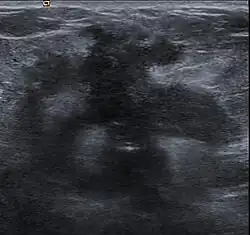

Desmoplastic reaction to breast cancer

Desmoplasia refers to growth of dense connective tissue or stroma.[2] This growth is characterized by low cellularity with hyalinized or sclerotic stroma and disorganized blood vessel infiltration.[3] This growth is called a desmoplastic response and occurs as result of injury or neoplasia.[2] This response is coupled with malignancy in non-cutaneous neoplasias, and with benign or malignant tumors if associated with cutaneous pathologies.[3]

Breast cancer

Clinical presentation of a lump in the breast is histologically viewed as a collagenous tumor or desmoplastic response created by myofibroblasts of the tumor stroma.[18] Proposed mechanisms of activation of myofibroblasts are by immune cytokine signaling, microvascular injury, or paracrine signaling by tumor cells.[18]